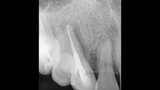

Treatment of the result of chronic activation of substance P